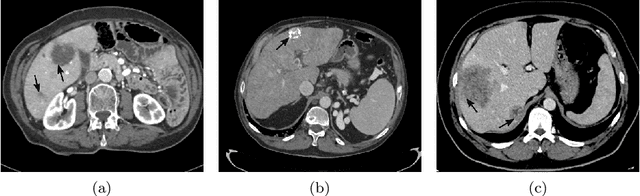

Abstract:Liver segmentation from abdominal CT images is an essential step for liver cancer computer-aided diagnosis and surgical planning. However, both the accuracy and robustness of existing liver segmentation methods cannot meet the requirements of clinical applications. In particular, for the common clinical cases where the liver tissue contains major pathology, current segmentation methods show poor performance. In this paper, we propose a novel low-rank tensor decomposition (LRTD) based multi-atlas segmentation (MAS) framework that achieves accurate and robust pathological liver segmentation of CT images. Firstly, we propose a multi-slice LRTD scheme to recover the underlying low-rank structure embedded in 3D medical images. It performs the LRTD on small image segments consisting of multiple consecutive image slices. Then, we present an LRTD-based atlas construction method to generate tumor-free liver atlases that mitigates the performance degradation of liver segmentation due to the presence of tumors. Finally, we introduce an LRTD-based MAS algorithm to derive patient-specific liver atlases for each test image, and to achieve accurate pairwise image registration and label propagation. Extensive experiments on three public databases of pathological liver cases validate the effectiveness of the proposed method. Both qualitative and quantitative results demonstrate that, in the presence of major pathology, the proposed method is more accurate and robust than state-of-the-art methods.